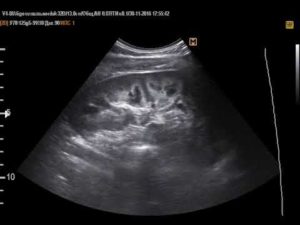

Информативным методом исследования почек является ультразвуковая диагностика. Часто на УЗИ обнаруживают изменения в мозговом слое паренхимы, так называемых пирамидках. Рассмотрим, как определить на УЗИ патологические изменения пирамидки в почках, что это дает для постановки диагноза.

УЗИ-диагностика пирамидок в почках

При УЗИ врач диагност рассматривает не только пирамидки, но и основные показатели почек. В норме они должны быть правильно, симметрично расположены, иметь ровный контур гиперэхогенной капсулы. Измеряются их размеры, положение и подвижность на вдохе. Эти показатели позволяют оценить общее состояние, наличие дефектов.

Затем рассматривается структура и строение паренхимы. Появление крупных образований высокой плотности вызвано образованием камней при мочекаменной болезни или развитием очагового воспалительного процесса.

Участки низкой плотности могут возникнуть при кисте почки, гематоме.

Особое внимание надо обратить на яркие, белые включения, которые указывают на наличие в почках склеротической ткани, кальцификатов и псаммомных телец (белково-жировые комплексы), присущих злокачественным новообразованиям.